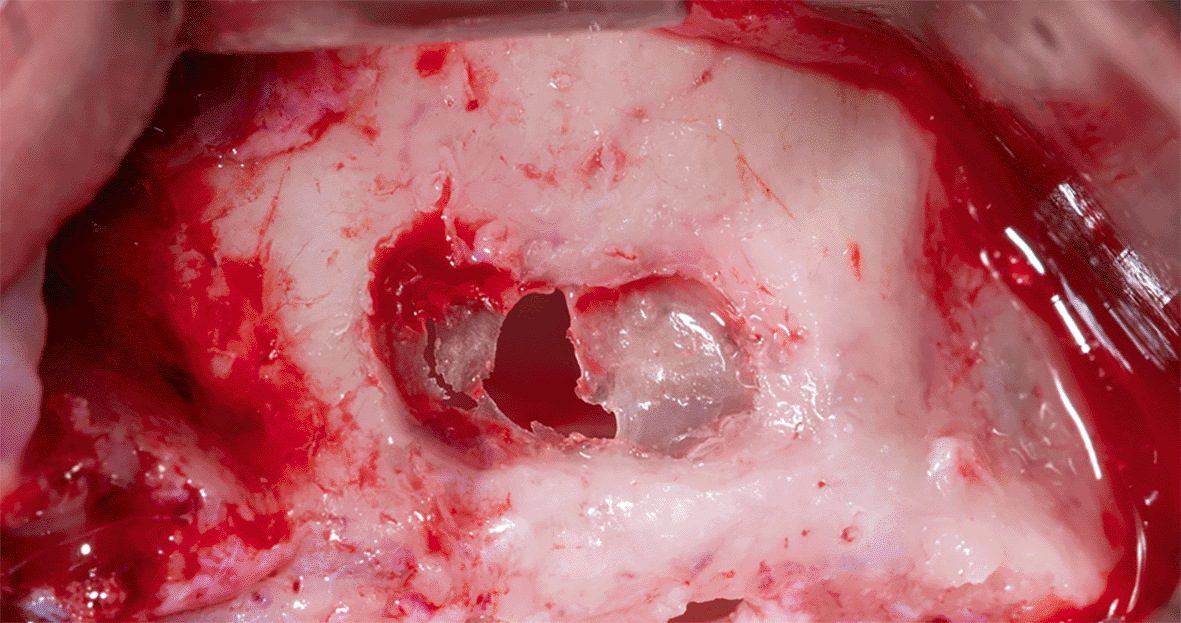

The sinus membrane was thin; therefore, it was torn when trying to open the lateral window and lift it, which prompted us to apply the pouch technique, which includes the following:

The membrane lifted from the inner sinus walls. Once the final intervention window is prepared ( Figure 4), we prepare the absorbable collagen membrane (Jason® membrane, Botiss, Germany) using the modified design performed by the researcher as it was used in this study for the first time ( Figure 5), where the membrane is measured and divided imaginarily into three parts as follows:

3928750d-b091-43c3-94bb-6b181f3845d3_figure4.gif

Figure 4. The final window after lifting schneiderian membrane.

After fixing the membrane to the palatal wall, the formed pouch is filled with a mixture of allograft (MYBONE, MSBIO, Korea) and xenograft (cerabone, Botiss, Germany) (30:70)10 until it is filled ( Figure 7). Part B forms the roof of the formed pouch, compensating for the torn sinus membrane.

3928750d-b091-43c3-94bb-6b181f3845d3_figure7.gif

Figure 7. Filling the formed pouch with the bone graft mixture.

After that, the lateral window is closed with part C of the collagen membrane and fixed using pins medial and lateral to the window ( Figure 8), each pin is 2 mm away from the window border.

3928750d-b091-43c3-94bb-6b181f3845d3_figure8.gif

Figure 8. Fixing the collagen membrane using pins to close the lateral window.

Mechanical fixing of the membrane using pins and filling the formed pouch contributes to bone graft stability in the formed sinus and prevents the displacement of both the membrane and the bone graft mixture.